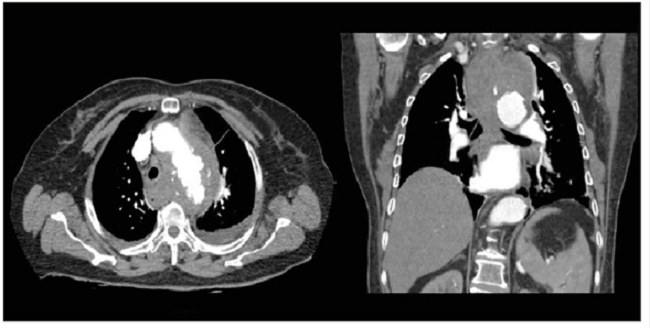

En la revisión de la angiotomografía, se encontraron signos sugestivos de ruptura contenida de la pared lateral derecha de la aorta torácica a nivel de la carina, con engrosamiento de las paredes del esófago proximal y pequeño derrame pleural libre bilateral (figura 1).

Fue sometida a una corrección endovascular de ruptura aórtica torácica, con endoprótesis recubierta (Medtronic Valiant VAMF2222C 150TE™), la cual se desplegó respetando el orificio de la arteria subclavia izquierda y se logró el cubrimiento exitoso del sitio de ruptura, sin evidencia posterior de extravasación con medio de contraste (figura 2).